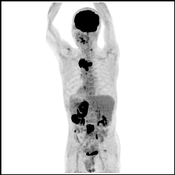

PET検査では、CT検査やMRI検査など、臓器の形から腫瘍の有無を診断する従来の検査法とは異なり、「がん細胞は正常の細胞に比べて多くのブドウ糖を取り込む」という性質を利用して、ブドウ糖にフッ素-18[18F]というごく微量の放射性物質(放射性同位元素)をくっつけた薬剤(以下FDG)を体内に注射します。すると、がん細胞は正常な細胞より多くのFDGを取り込みます。そこから放出される微量の放射線をPETカメラでとらえて、がん細胞の代謝・機能を調べることで、がんの発見に威力を発揮するというわけです。

◎がんの発見、転移、再発の診断に有用です。

◎一度の検査でほぼ全身を見る事が可能です。

当院では、PET検査と同時にCT検査が行える最新鋭機器『PET-CT』を導入しました。これにより、検査時間の短縮はもちろんのこと、PETによる細胞の機能診断画像とCTによる形態診断画像を重ね合わせることで、診断精度が大幅にアップします。

| <PET/CT Fusion画像> | <PET/CT Fusion画像> | <PET画像> | <MIP画像> |